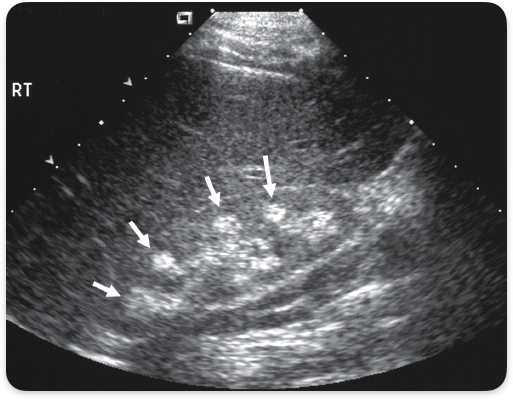

Adpkd , autosomal dominant polycystic kidney disease. Bilateral enlarged kidneys, cysts in other organs.